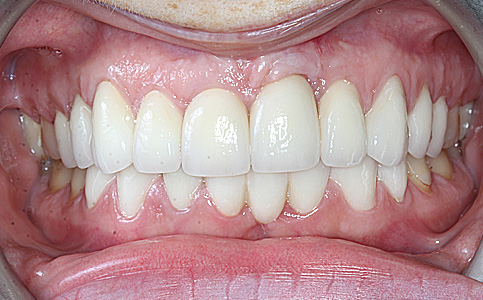

Przykład pełnej rehabilitacji protetycznej obejmujący leczenie biologiczne, uzupełnienie braków zębowych implantami oraz korony pełnoceramiczne w łuku górnym i dolnym. Spektakularna metamorfoza uśmiechu wykonana przez zespół Centrum Stomatologii i Ortodoncji FRESHmed odmieniła życie Pacjenta dodała pewności siebie i sprawiła, że z chęcią się uśmiecha.